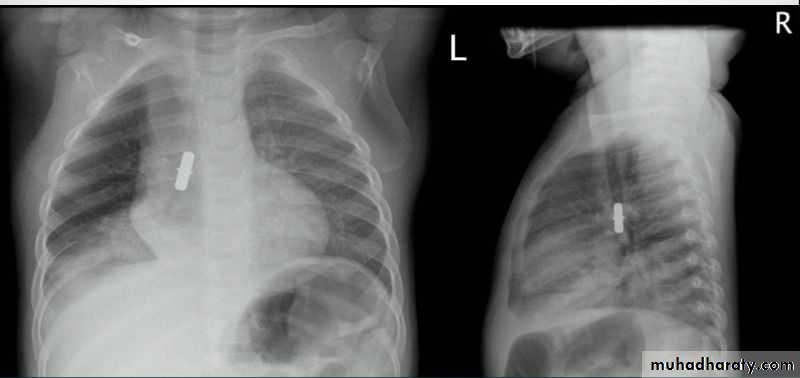

Foreign body in right bronchus

Foreign body in bronchus

Foreign body in esophagus

Foreign body in right esophagus